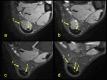

The aim of the study was to check if the subtendons of the Achilles tendon can be identified in vivo on MRI in the midportion of the tendon. The relation of the plantaris tendon to the Achilles tendon was also examined. A retrospective study of 200 MRI of ankle joints including the Achilles tendon was conducted. Statistical analysis of the correlation between the possibility of identifying the subtendons and the side, gender, presence of the central soleus tendon and plantaris tendon variation was performed. The inter-observer agreement between two reviewers in their evaluation of the subtendons was assessed using kappa statistics. The subtendon from the lateral head of the gastrocnemius muscle was identified in 65% (k = 0.63) and was located in the anterior part of the Achilles tendon. The subtendon from the soleus muscle was recognized in 12% (k = 0.75) comprising anterior part of the tendon. In 6% the subtendon from the medial head of the gastrocnemius muscle was identified (k = 0.58). The central soleus tendon was identified in 85% of cases. Statistical analysis shows the weak correlation of the presence of the central soleus tendon and the possibility of identifying the subtendon from the soleus muscle. The plantaris tendon was directly related to the insertion of the Achilles tendon in 42.5%. Identification of the subtendons of the Achilles tendon on MRI is challenging, and most often it is only possible to find the subtendon of the lateral head of the gastrocnemius muscle.